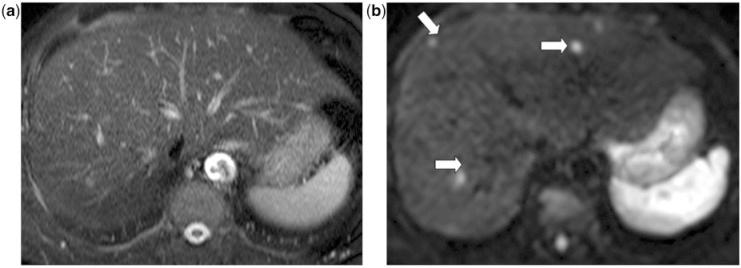

Diffusion-weighted imaging of the liver: an update.

Diffusion-weighted magnetic resonance imaging (DW-MRI) is now widely used as a standard imaging sequence for evaluation of the liver. The technique is easy to implement across different MRI platforms, and results in enhanced disease detection and characterization. With careful implementation, the quantitative apparent diffusion coefficient derived shows good measurement reproducibility, which can be applied for tissue characterization, the assessment of tumour response and disease prognostication. There is now a body of evidence that highlights the relative strengths and limitations of the technique for the assessment of liver diseases. The potential for more sophisticated analysis of DW-MRI data is currently being widely investigated.

扩散加权磁共振成像(DW-MRI)现在被广泛用作评估肝脏的标准成像序列。该技术易于在不同的 MRI 平台上实施,可提高疾病检测和特征描述的能力。通过仔细实施,所得到的定量表观扩散系数具有良好的可重复性,可用于组织特征描述、肿瘤反应评估和疾病预后预测。现在有大量证据强调了该技术在评估肝脏疾病方面的相对优势和局限性。目前,人们正在广泛研究对 DW-MRI 数据进行更复杂分析的可能性。